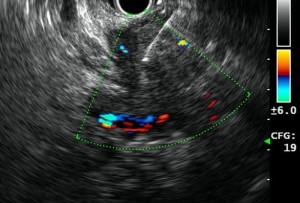

Endoscopic ultrasound (EUS) is an endoscopic procedure for imaging of the upper gastrointestinal tract (oesophagus, stomach, and duodenum), and the pancreas to biliary system (bile ducts, gallbladder, and pancreas) using a flexible endoscope equipped with a small specialized ultrasound probe.

Before undergoing EUS, patients are given sedation. A thin tube is inserted through the patient’s mouth and led down into the stomach. Once in the stomach, a small ultrasound probe at the tip of the tube emits soundwaves which produces a clear image of the desired area (such as the pancreas, digestive tract, or stomach). If masses or other signs of disease are found, a small biopsy will be taken for testing (with by EUS guided Fine Needle Aspiration (FNA).